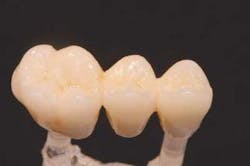

When the framework was returned to the laboratory, it was examined for fit on a master model. Initial fit was good. Small adjustments in angulations of the emergence profile were made and the facial margins were cut back for porcelain margins to increase gingival illumination. Although a ridge-lap pontic was to be utilized, the stone was relieved enough to create pontic pressure against the tissue and ensure the development of a small gingival cuff, creating the illusion of natural emergence.

The ceramic build-up was started with the application of the porcelain margin material and some highly chromatic modifiers to camouflage the substructure. These layers were fired under vacuum in a porcelain furnace to full maturity. Subsequent layers of dentin and enamel powders were built and fired to replicate the optical qualities of the patient's natural dentition. Anatomical features were built in with a porcelain brush, rather than ground in with a high-speed handpiece, to create more natural contours. Final surface texture was achieved by grinding with a 850-016 diamond bur (Brasseler), then the bridge was fired to a low glaze. A diamond-impregnated rubber polishing wheel (Brasseler) was used to smooth areas to be highlighted, and diamond polish (Brasseler) accomplished the final surface luster. The bridge was fit to a fresh solid model to verify the interproximal contacts, tissue adaptation, and occlusion, then returned to Dr. Jones for delivery.